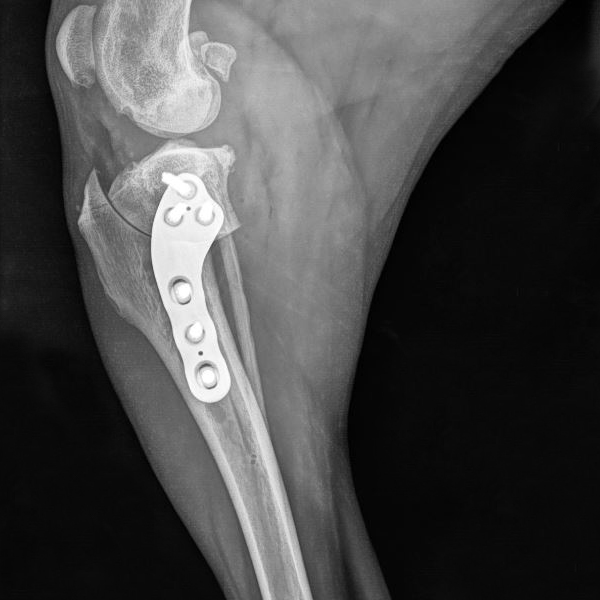

Case Description: The patient is a 13 year old Norwich Terrier diagnosed with a rupture of the anterior cruciate ligament, and received surgical treatment by TPLO.

“The plates of the LeiLOX System provide the opportunity to insert screws at different angles, which is critical in small patients to prevent the screw from entering the joint cavity. The X-ray shows an example of screw insertion at different angles. The video shows the dog walking 2 weeks after the operation.”